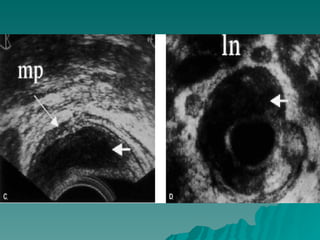

CANCER DE COLONY RECTO DIAGNOSTICO  Historia clínica.  Exploración física ( tacto rectal ).  Laboratorio clínico y Rx. tórax, MT ( ACE ).  Colon por enema.  Colonosocopia ( biopsia ).  TAC  Ultrasonido endoluminal.

 Ultrasonido endoluminal.